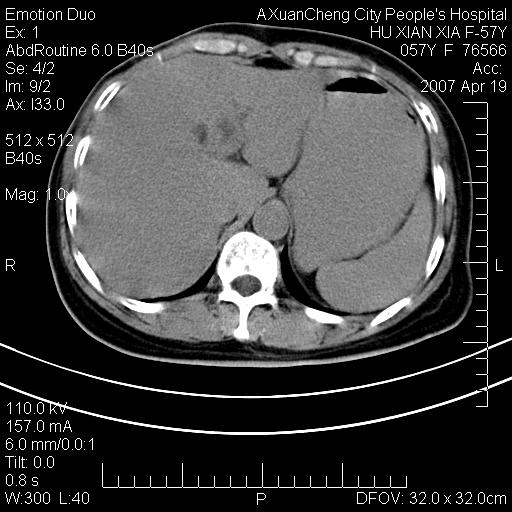

标题: CT7778:[原创]F,57Y腹痛待查,胸片提示肺部占位,应当很典型 [打印本页]

标题: CT7778:[原创]F,57Y腹痛待查,胸片提示肺部占位,应当很典型

胸片提示肺部占位

1.双侧肾上腺占位,转移首先考虑。

2.肝硬化,门静脉高压;肝左叶内侧段病灶建议增强。

双侧肾上腺结节样肿块,结合肺部肿块,考虑肺癌肾上腺转移。

双侧肾上腺及腹膜后淋巴结增大,结合胸片提示肺部占位,考虑肺癌双侧肾上腺及腹膜后淋巴结转移.